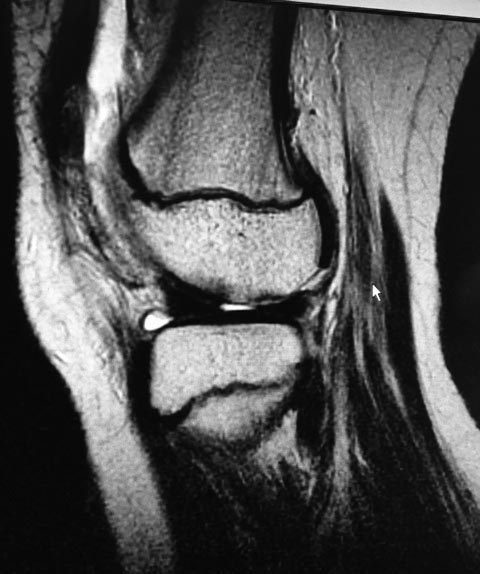

Только сейчас присмотрелся - фрагмент крупный. Ложе на опорной поверхности мыщелка бедра. В послеоперационом периоде потребуется фиксированное сгибание под углом близким к 90 градусов. Нет опыта работы с детьми. Если продумать послеоперационную реабилитацию, то может быть...

Да, при огромных внутрисуставных фрагментах даже в застарелом случае имеется смысл провести фиксацию, потому что внутрисуставные хрящи как разновидность гиалинового хряща питание получают из синовиальной жидкости диффузным методом. Феномен можно увидеть при болезни Кёнига или рассекающем остехондрите, когда участок хряща отслаивается и без изменении может находиться очень долгое время внутри сустава.

Только при фиксации фрагмента необходимо обратить внимание на подготовку питающего ложа для костного основания и на стабильность фрагмента. Винты создают более хорошую стабильность, чем тонкие стержни, но головка винта будет сидеть в суставной поверхности, поэтому предлагается Smart стержни в разных направлениях.